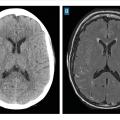

Il est capital de réaliser une imagerie artérielle dès la phase diagnostique pour planifier la suite de la prise en charge. Dans cette indication, l’angio­scanner a une meilleure sensibilité que l’angio-IRM en temps de vol pour la détection des anévrismes de taille inférieure à 3 mm. Une attention particulière est portée aux sites de développement préférentiel des anévrismes dits « de bifurcation ». (fig. 3).